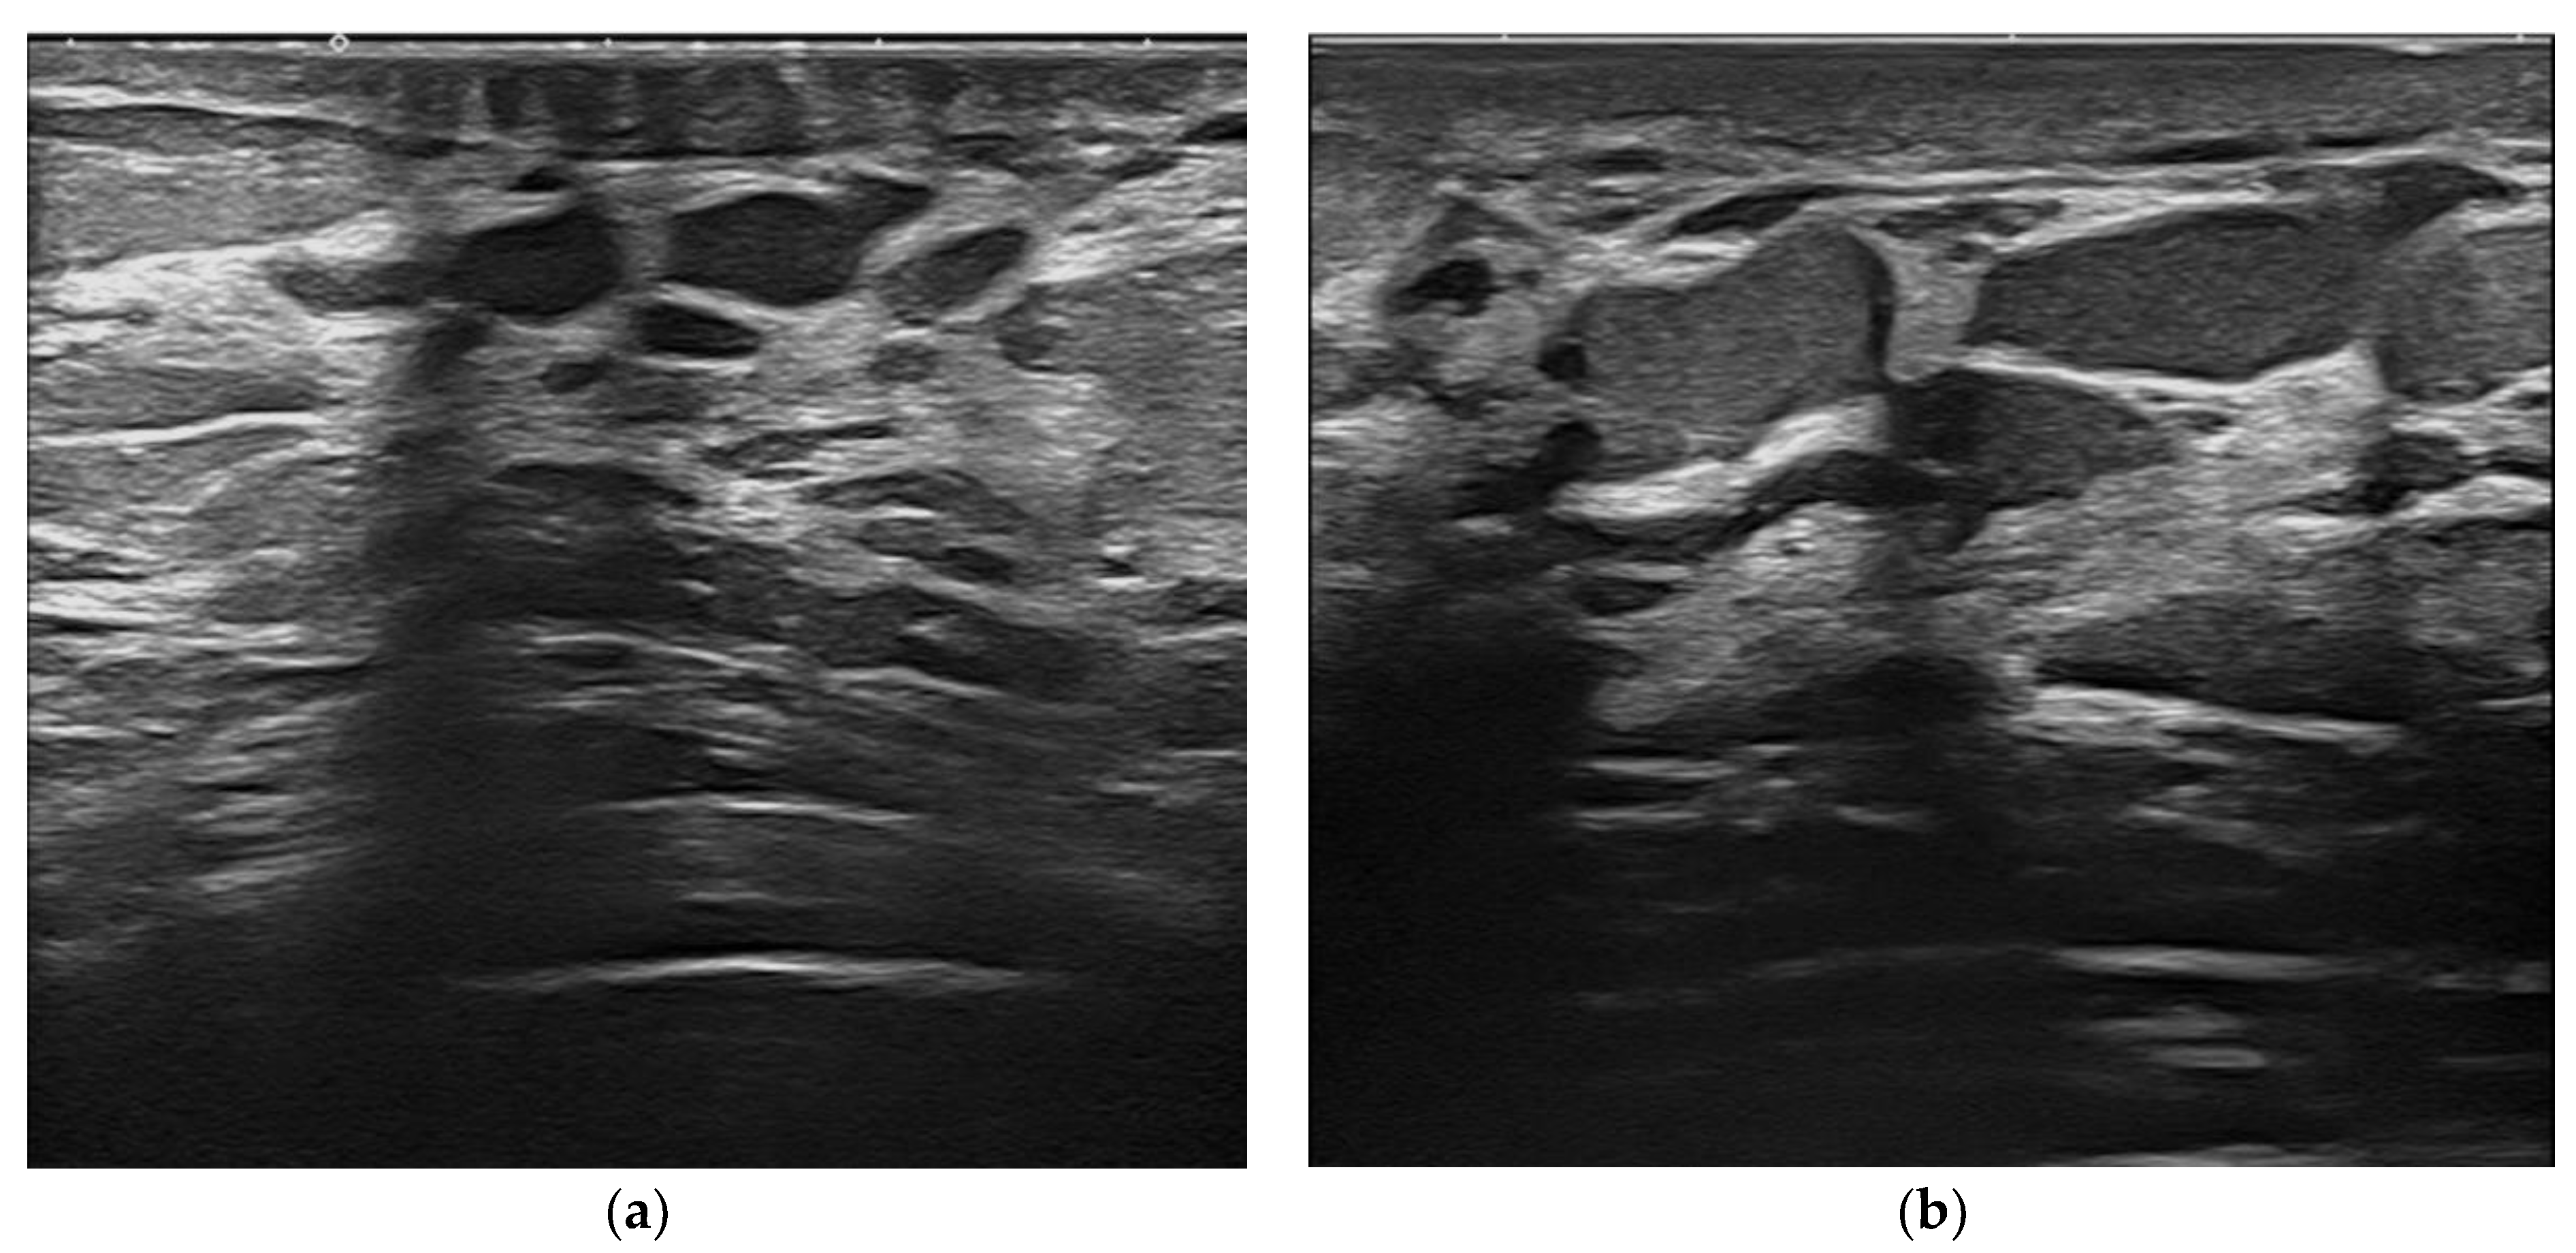

Figure 6. Intraductal papilloma. Retroareolar, oval hypoechoic nodule without flow signals (8 × 4 mm). Appearance at 15 MHz (a). When imaged at 22 MHz (b), the lesion is clearly located in the lumen of a duct and exhibits some internal vessels under power-Doppler imaging.